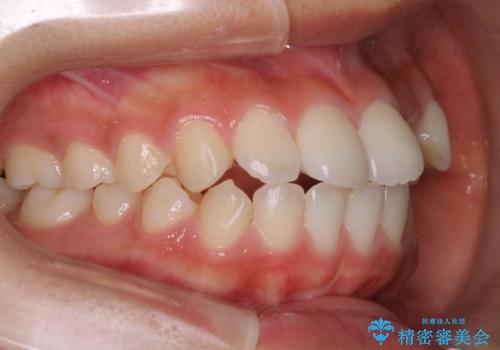

前歯が八重歯でガタガタ ワイヤーによる抜歯矯正